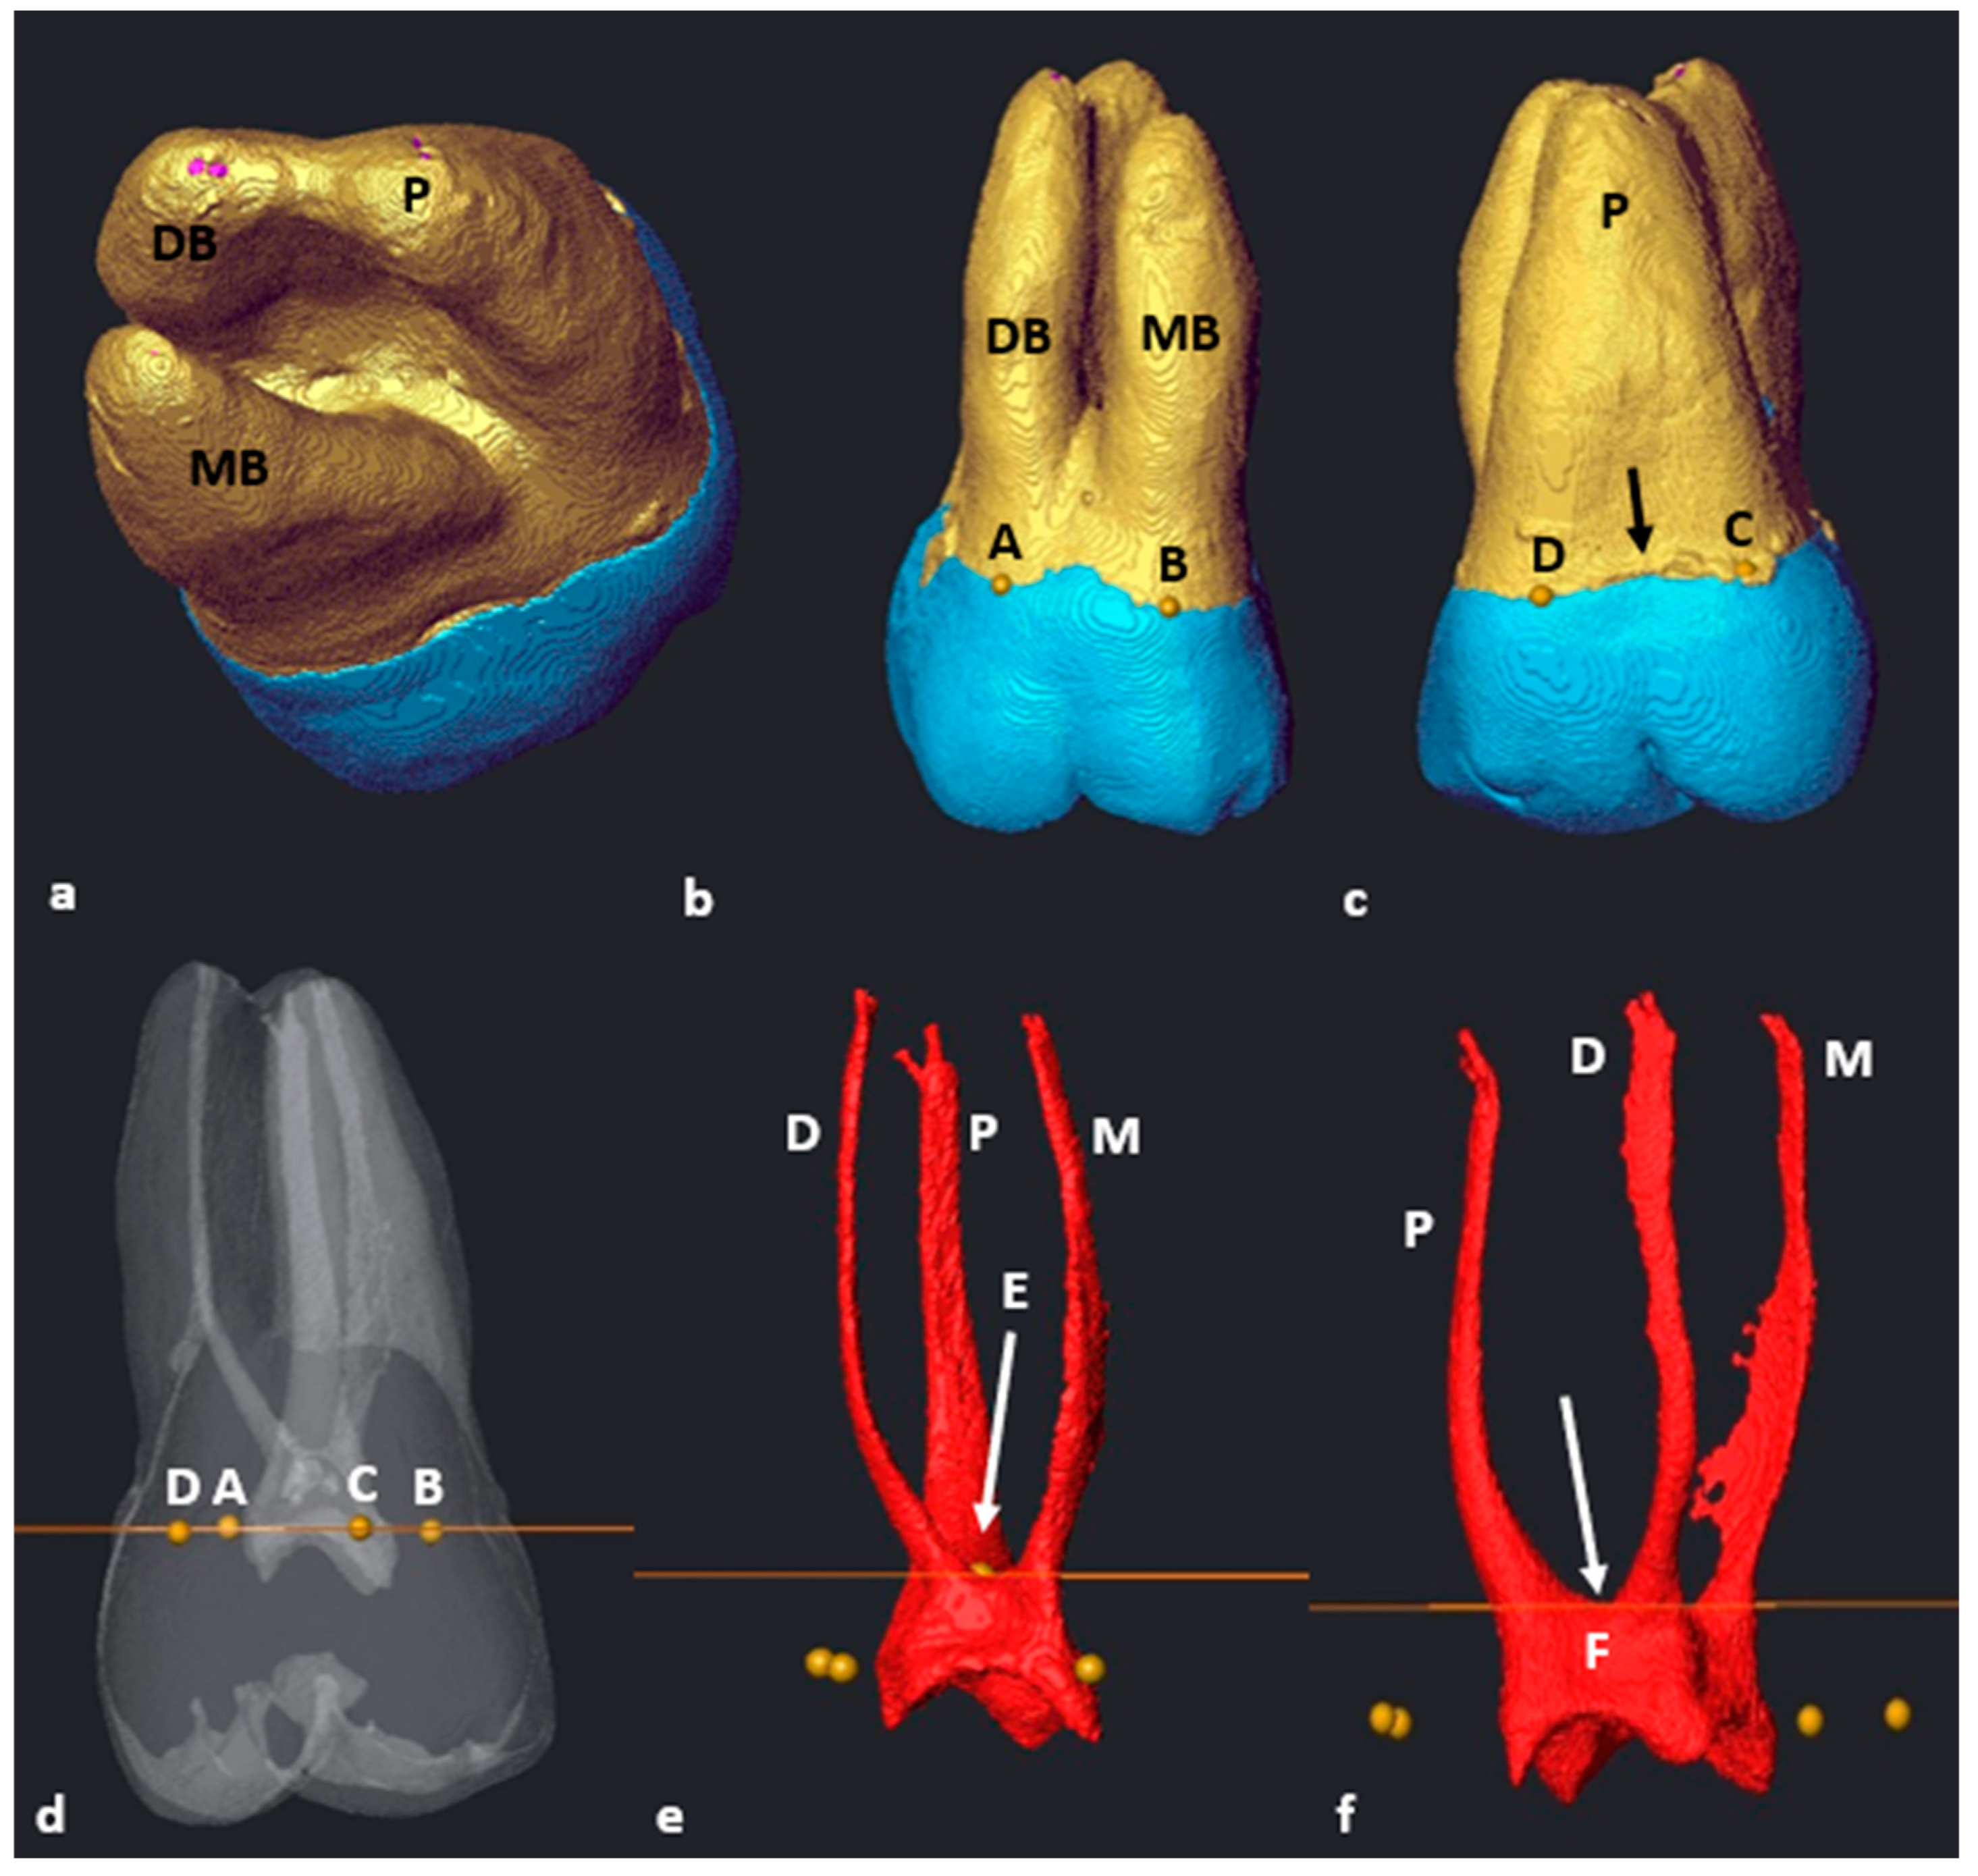

3.1. Mandibular First Molars: Two Rooted